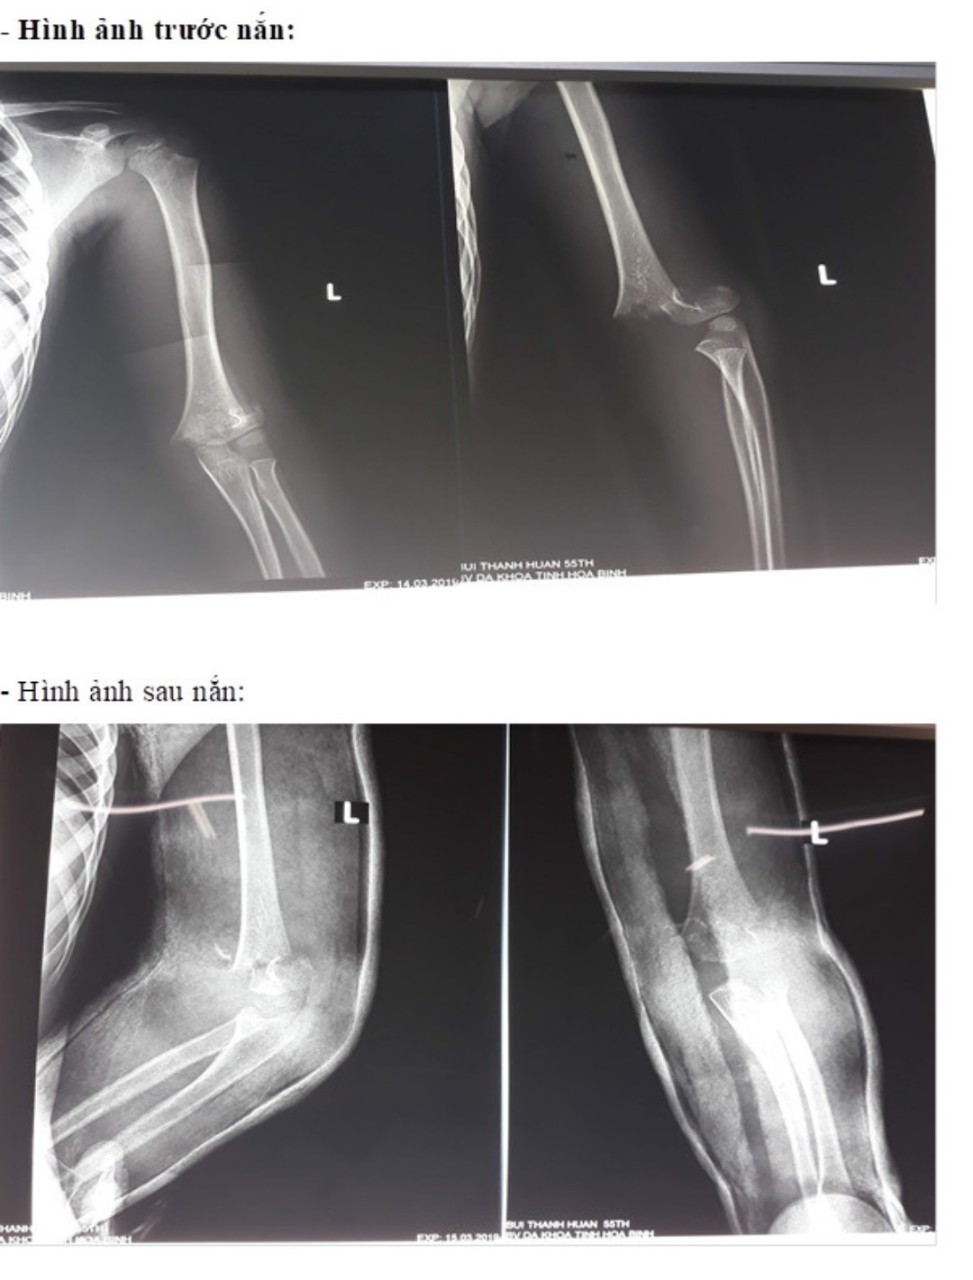

Hình ảnh trước nắn (ảnh trên) và sau nắn (ảnh dưới)